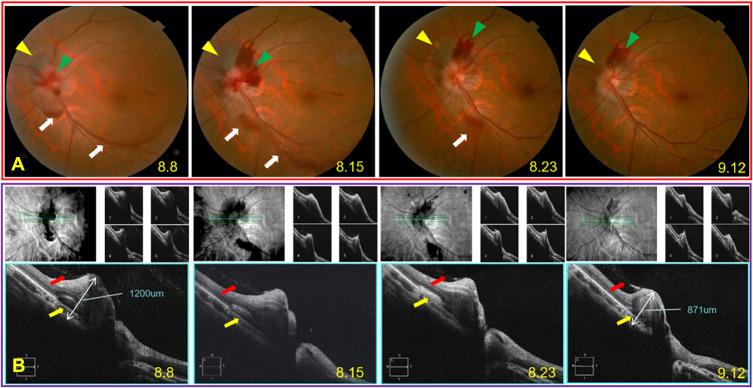

Three myopic patients with IHAPSH shared a similar clinical course and multimodal imaging appearance. The symptom was sudden dark shadows floating in the affected eye with mild visual blurring. Fundus photography showed hemorrhage in intrapapillary and subretinal, as well as optic disc bulges on the nasal side with local vitreoretinal separation in the affected eyes. OCT confirmed intrapapillary and subretinal hemorrhage with obviously elevated optic papilla in the affected eye and local vitreoretinal separation at the temporal side of optic disc together with vitreoretinal adhesion at the superonasal edge. FFA&ICGA ruled out optic drusen and neovascularization. B-ultrasonography in one case revealed optic disc bulge in the affected eye with tight traction by local detached vitreous posterior limiting membrane at the edge. The overall visual prognosis was excellent and the bleeding could be completely absorbed.

IHAPSH tends to appear in young women with myopia. The mechanism may be attributed to an incomplete posterior vitreous detachment (PVD), followed by a tightly vitreous-papilla adhesion and concentrated traction to the superonasal part of the tilted small optic disc.